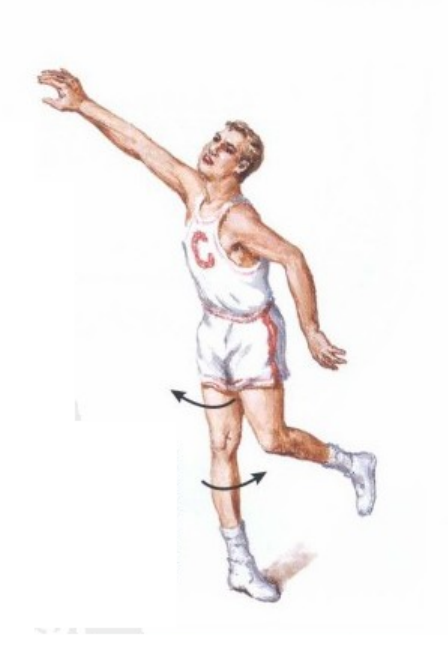

2、非接触性损伤(最常见)

是指在跑步、跳跃等运动过程中突然减速或改变方向,膝关节突然减速、扭转和其他对关节施加剪切应力所导致的前交叉韧带损伤。

篮球比赛中,当球员跳跃后着地膝关节过度伸直且胫骨处于内旋位时,常发生前交叉韧带撕裂。